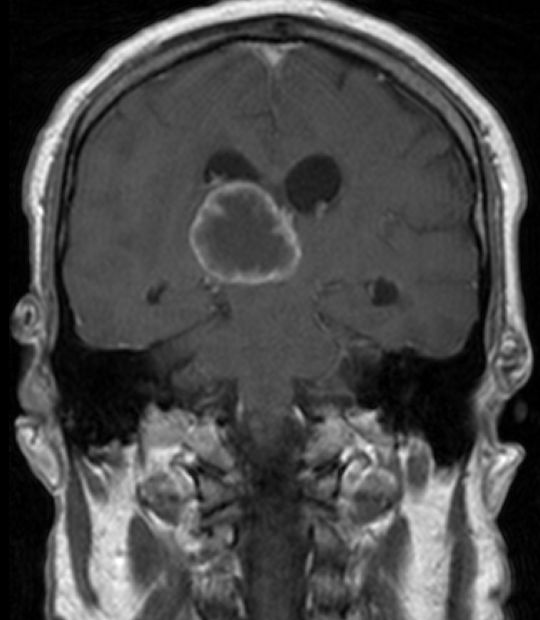

| MRT: multiple Hirnmetastasen | Adenokarzinom der Lunge. MRT-Untersuchung des Hirns. | |||

| MRT: multiple Hirnmetastasen | 70-jähriger Mann, der vor einem Jahr ein Adenokarzinom des rechten Lungenmittellappens hatte. MRT-Untersuchung des Hirns, T1-Sequenz mit Kontrastmittel. Klinisch keine Symptome! | |||